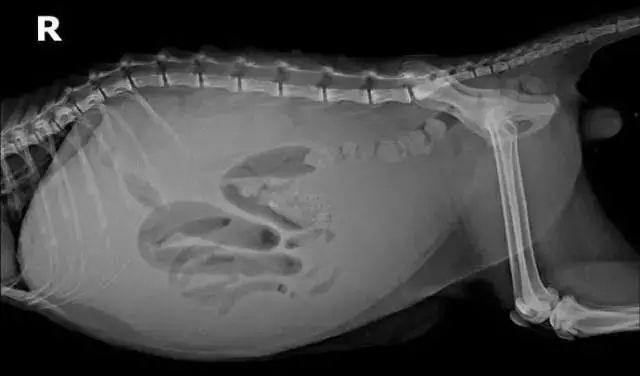

从另一个角度说,有时候腹水没那么明显的猫咪也可能患上猫传腹,因为干性传染性腹膜炎产生的腹水并不多,所以看上去肚子并不算大,但也是感染了猫传腹。不过猫腹水也不全都是猫传腹,最终只有50%左右的病例会确诊为FIP,腹腔穿刺、腹部X光都是有效诊断方法。